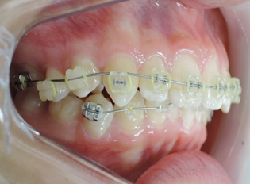

当院の治療では、上顎から矯正装置を装着していきます。

その後下顎の矯正装置を装着します。

この過程で歯並びが整いMEAW(マルチループ)を装着しやすくなります。

MEAW(マルチループ)を使用する事で、上顎前突(出っ歯)や咬合高径(咬み合わせの高さ)の改善をしています。

☆治療途中

MEAW(マルチループ)を使用する事で、上顎前突(出っ歯)や咬合高径(咬み合わせの高さ)を改善して2年6ヶ月で非抜歯での治療で綺麗な歯並びになりました。